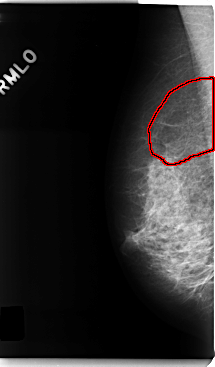

C_0193_1.RIGHT_MLO

RIGHT_MLO LINES 4760 PIXELS_PER_LINE 2784 BITS_PER_PIXEL 12 RESOLUTION 50 OVERLAY

FILE: C_0193_1.RIGHT_MLO.OVERLAY

TOTAL_ABNORMALITIES 1

ABNORMALITY 1

LESION_TYPE CALCIFICATION TYPE PLEOMORPHIC DISTRIBUTION SEGMENTAL

ASSESSMENT 5

SUBTLETY 5

PATHOLOGY MALIGNANT

TOTAL_OUTLINES 1

BOUNDARY